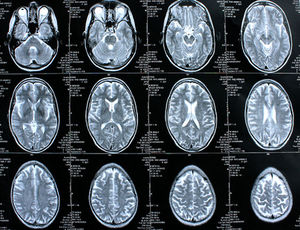

Gehirn-Scans: deutlich mehr Tumore bei Akademikern (Foto: pixelio.de, Rike) |